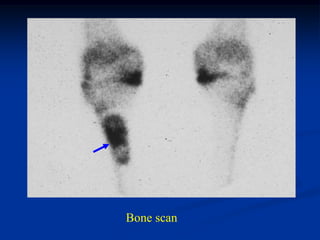

Case #120

38 year female

enchondroma

distal femur

Bone scan